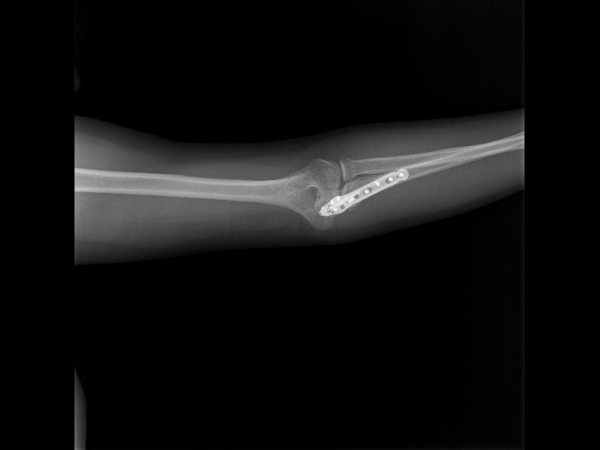

TRUE LOCK Olecranon Anatomic Plates are precontoured for anatomic fit. No need to bend during teh surgery.

Elongated Combi hole in the neck and shaft facilitate plate adjustment and allow locking or compression options.

Long proximal extension and multiple screw options to secure small olecranon fragments to help neutralize the forces of the triceps muscle.